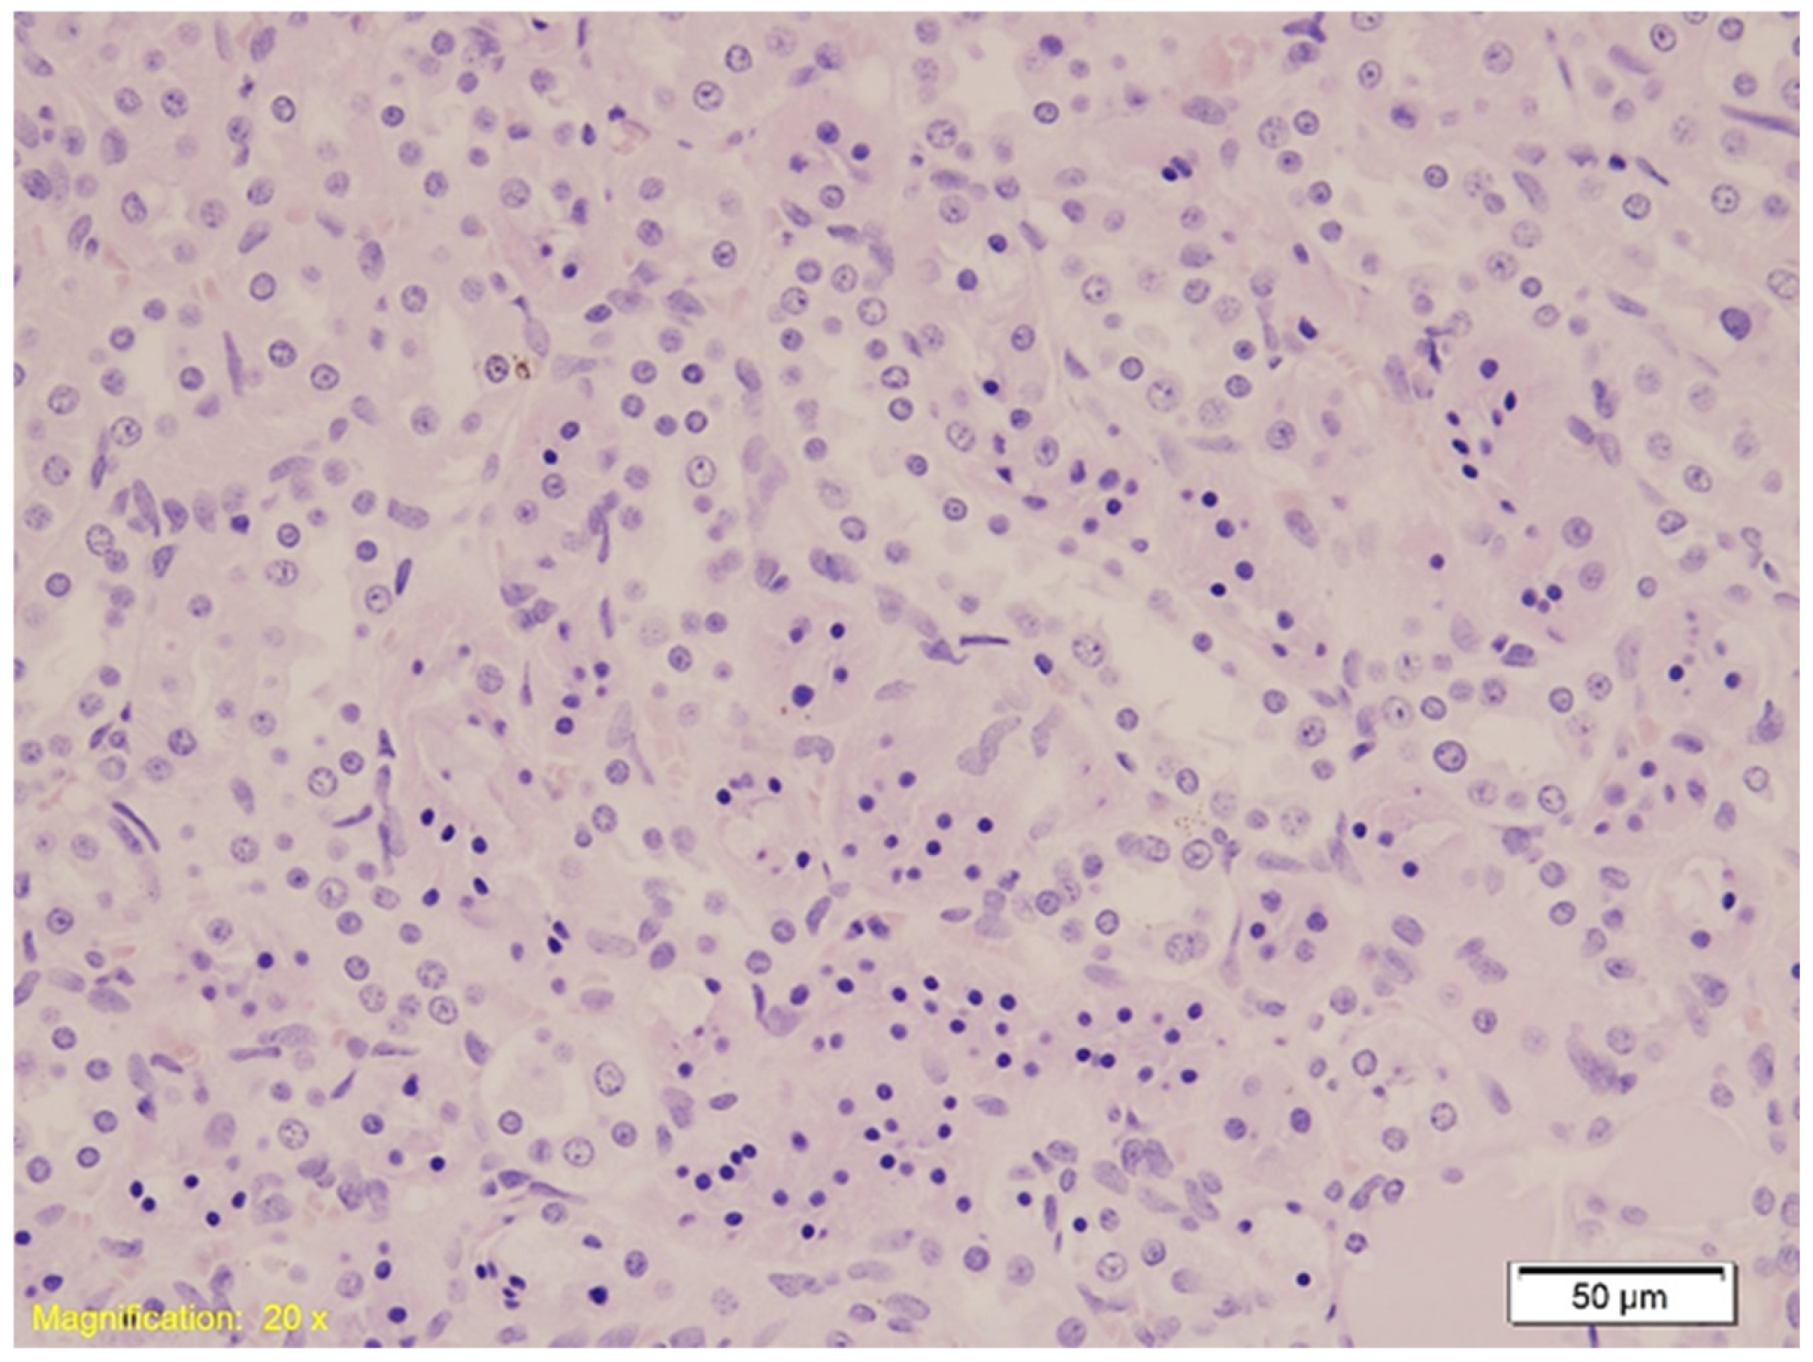

| Kidney | Hydropic and vacuolar degeneration, congestion; occasional acute tubular injury (eosinophilia, swelling, pyknotic nuclei); minimal lymphocytic infiltrate in interstitium. | Similar findings as Group K; occasional acute tubular injury and lymphocytic infiltrate. | Similar findings as Group K; occasional acute tubular injury and lymphocytic infiltrate. |